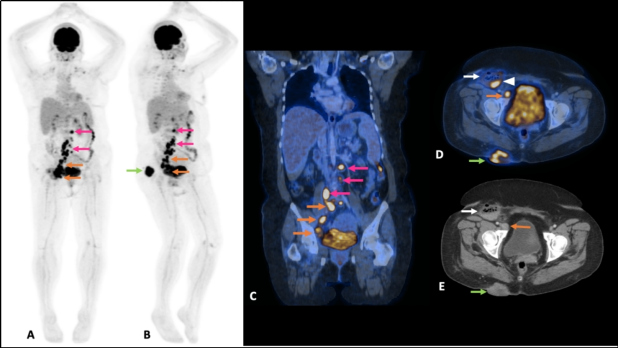

Mujer de 49 años con antecedente de leucemia de células pilosas (tricoleucemia) de riesgo bajo, en remisión completa. En septiembre 2020 presentó aumento de volumen en región supero-interna del glúteo derecho; ante la sospecha de una infección de tejidos blandos recibió antibióticos, sin mejoría. El mismo mes fue valorada en nuestra institución por la presencia de una neoformación cutánea dolorosa en glúteo derecho. Se realizó ecografía de la lesión dérmica (fig.1) y una tomografía de abdomen y pelvis en fase venosa, donde se observó una lesión sólida de 45 x 24 x 41 mm, con márgenes bien definidos y lobulados. Además se detectaron adenopatías ilíacas comunes, en cadena ilíaca interna derecha y en región inguinal homolateral, de entre 15 y 51 mm. Referida la paciente al servicio de Dermatología, la lesión fue descrita como una neoformación de aspecto nodular, cupuliforme, de 4 x 5 cm de diámetro, superficie lisa y violácea, sólida, a la dermatoscopía con patrón reticular y áreas rosas y blancas, sin estructura (fig. 2). Posteriormente se realizó biopsia por huso de la lesión glútea, con reporte de patología de carcinoma invasor de células de Merkel con invasión a dermis profunda (CK-, CK20+, Cromogranina +, Sinaptofisina -, Ki67 80%, CD56+, CD117+); además se tomó una biopsia excisional del conglomerado ganglionar inguinal, que confirmó la presencia de metástasis. Como parte de su estadiaje, en enero de 2021 se realizó un estudio PET/CT con 18F-FDG que documentó incremento focal del metabolismo en la lesión, así como adenopatías hipermetabólicas cervicales, retroperitoneales, ilíacas bilaterales e inguinales derechas. Debido a un sangrado no controlado del tumor, se procedió a la resección de la lesión glútea y colgajo de muslo posterior sin complicaciones, reportando márgenes quirúrgicos negativos. Al tratarse de una enfermedad metastásica, se administró quimioterapia a base de etopósido y cisplatino, en 5 ciclos desde marzo a junio y se realizó nuevo PET/CT con 18F-FDG para evaluar respuesta a tratamiento. Por presentar oligo-progresión ganglionar (adenopatía pericecal hipermetabólica), recibió radioterapia corporal estereotáctica (SBRT) 45Gy en 6 sesiones desde junio a julio de 2021. En agosto se realizó un nuevo PET/CT donde se observó desaparición de la adenopatía antes mencionada y una nueva lesión nodular de bordes lobulados en región glútea derecha de 36 x 32 mm con SUV máximo de 15,6. La fig. 4 muestra el MIP de los 3 estudios PET/CT: inicial, post-resección + quimioterapia y post-radioterapia. La paciente continuó su tratamiento experimentando respuesta completa aunque más tarde se comprobó recaída local y ganglionar, todo lo cual fue documentado mediante PET/CT, no incluído en esta publicación.